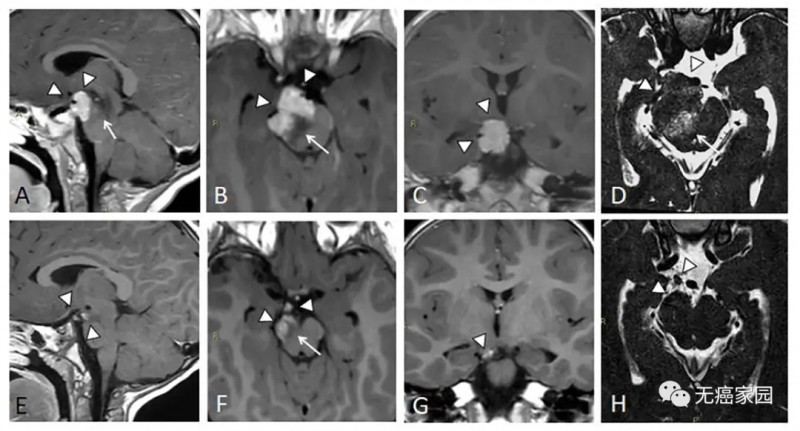

患儿4个月时手术活检查出:浸润性透明细胞脑膜瘤(WHO II级),Ki67增殖指数为7%。1岁时肿瘤持续增大,年龄太小无法手术切除,遂采用质子治疗。

通过观察:质子治疗后39个月后的复查核磁结果,显示肿瘤得到控制,H显示肿瘤体积肉眼可见缩小90%。